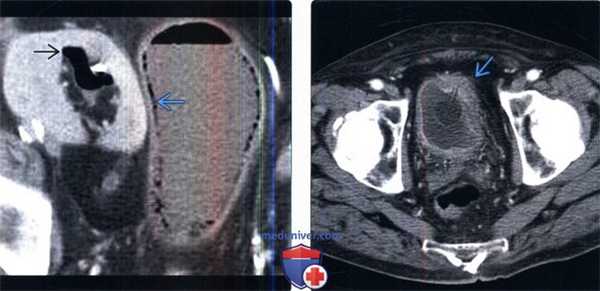

(Слева) КТ с контрастированием, аксиальный срез: газ в просвете и стенке мочевого пузыря, как и в чашечно-лоханочной системе аутотрансплантата, что соответствует эмфизематозному циститу/пиелиту. В анамнезе отсутствуют свежие данные инструментального исследования, объясняющие причину наличия интравезикального/интраренального газа.

(Справа) КТ с контрастированием, аксиальный срез: эксцентричное утолщение стенки мочевого пузыря с окопопузырными воспалительными изменениями, сравнимые с циститом, вероятно вследствие хронического раздражения постоянным катетером. Гиперемия стенки свидетельствует больше в пользу цистита, чем новообразования.